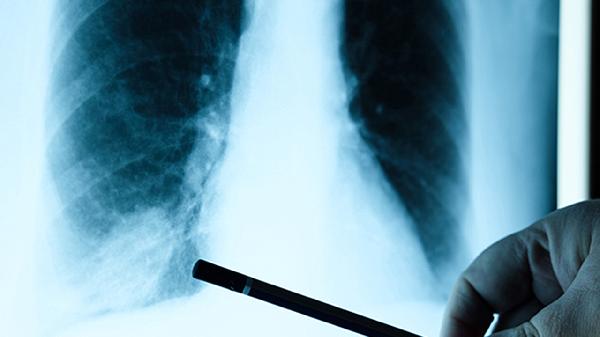

一、认识肺结节的危险警戒线

1.直径大小的秘密

临床经验表明,5毫米就像一道自然分界线。小于这个尺寸的结节就像沙粒掉进沙滩,恶性概率不到1%;但当直径突破8毫米,风险曲线会突然变得陡峭。特别需要注意的是,那些在随访复查中"悄悄长大"的结节,即便增长速度缓慢,每年增大2毫米也值得提高警惕。

2.形态特征透露的信号

边缘光滑的结节往往像性格温和的邻居,而那些带着毛刺、分叶的结节则更像神秘来客。密度也是重要参考指标,实性结节虽然检出率高,但亚实性结节(特别是磨玻璃样变)有时反而更需要专业评估。